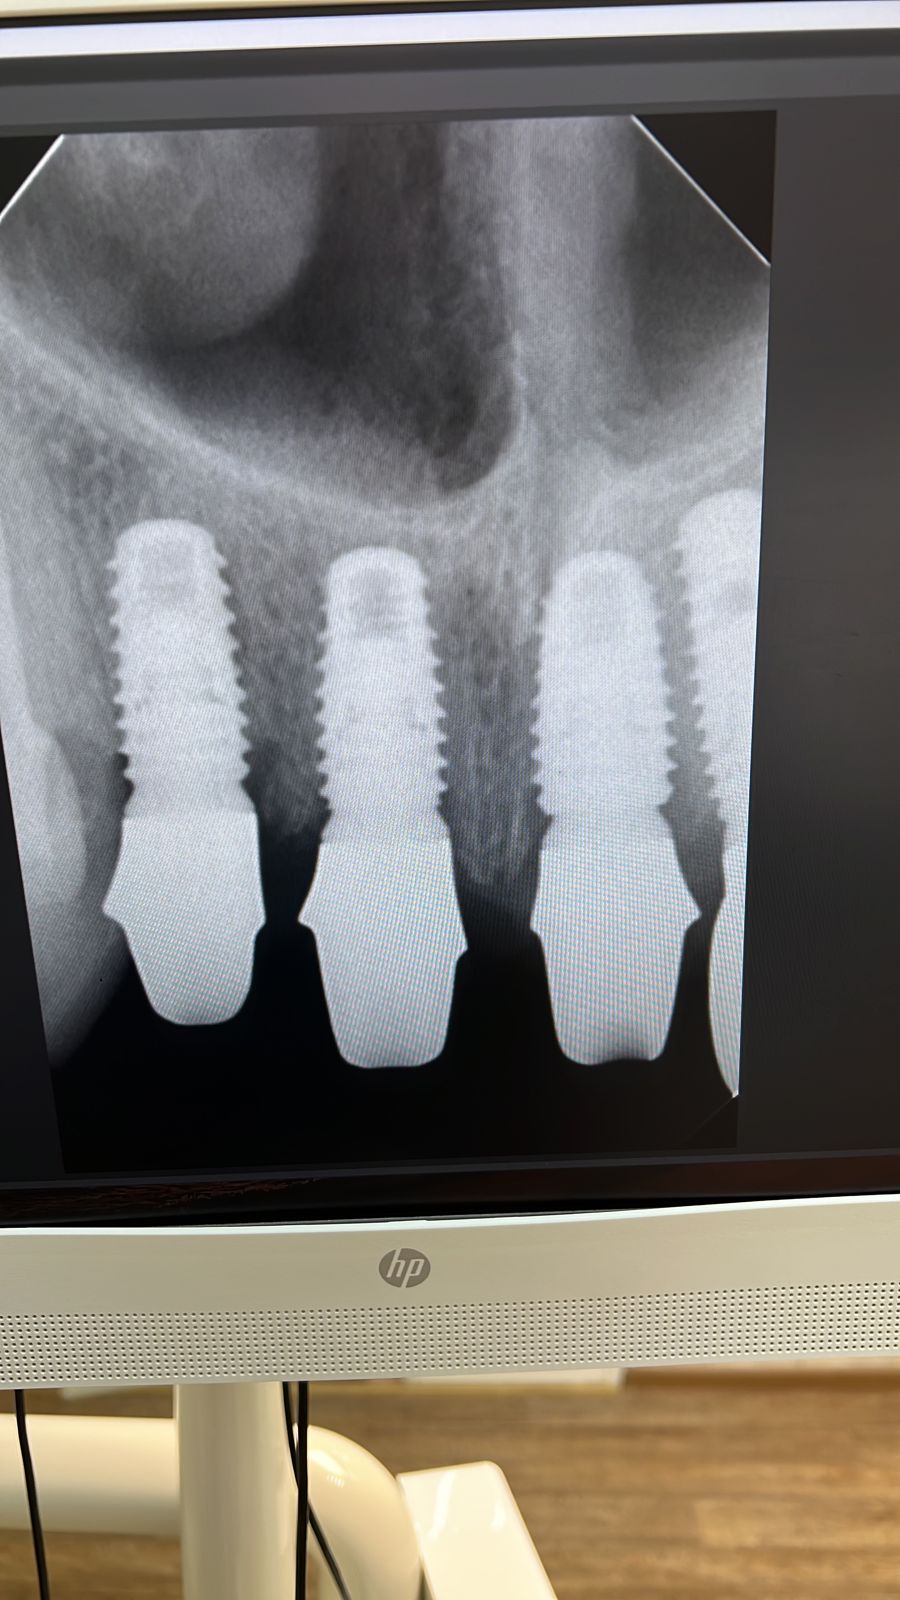

Имплантация зубов

Установлено 4 имплантанта Osstem во фронтальном участке верхней челюсти.

Протезирование выполнено коронками из оксида циркония с фиксацией на абатменты из оксида циркония.